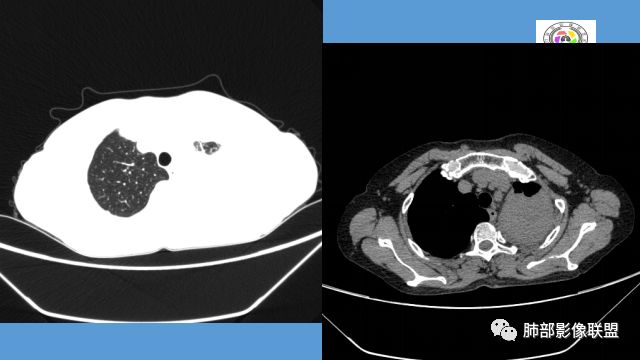

左上胸缩小,但是左上叶部分实变,边缘膨隆,内部有含气支气管,粘液栓,近端支气管堵塞

前端支气管通畅,部分稍扩张,走形自然

实变区支气管内粘液栓明显

上叶支气管堵塞处稍萎缩、凹陷,附近壁增厚,内可见小点状钙化

树芽征、小叶间隔增厚,淋巴结, 内部血管走形自然

分析:支气管粘液栓、支气管堵塞处萎缩、钙化,支气管通畅处部分扩张,树芽征——提示结核。

病灶膨隆明显,支气管堵塞,附近壁增厚,是否需要警惕恶性?

支气管壁软骨存在且连续,没有被破坏掉,支气管壁局部通畅,提示支气管壁没破坏,那么近端支气管癌肿不考虑。远端有树丫征,病灶周围很多钙化,所以结核一定有。

电话随访:湘雅医院纤维支气管镜检查:左肺上叶支气管外压狭窄、粘膜病变。穿刺未见肿瘤细胞,考虑结核,抗结核治疗后病情较前好转。

1.双肺多发病灶,结节影、树丫影,边缘分布……病灶符合继发性肺结核。

2.左肺上叶大片实变影,密度不均,体积轻度增大,注意轻到中度强化及血管影未见破坏、未见坏死空洞……病灶更符合炎症,而不大支持干酪性结核及肺鳞癌等,后两者的破坏能力是比较强的。

3.支气管阻塞,沿途可见钙化及液性潴留……更符合支气管内膜结核。

综上,双肺继发性肺结核诊断应当成立;左肺上叶大片影,以支气管内膜结核伴阻塞性炎症解释更为合理。